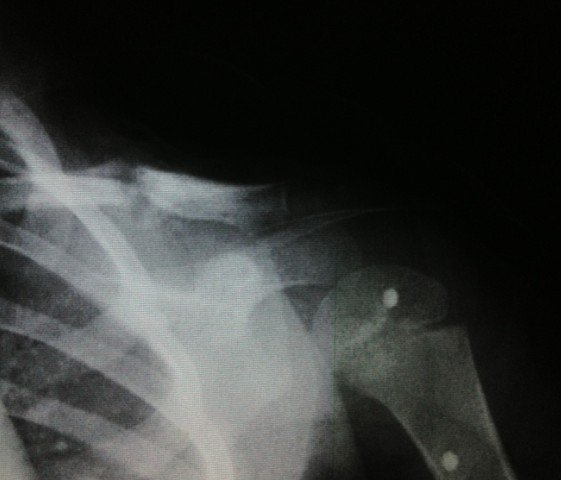

宝宝3岁半出车祸左锁骨骨折

患者信息:女 3岁 贵州 遵义 病情描述(发病时间、主要症状等):2012.10.7日发送车祸,X片确诊为左锁骨骨折。当天就打上八字绷带。想得到怎样的帮助:现在已经自行把八字绷带取下,请问这样做可以吗?因为孩子的腋下已经开始有轻微溃烂的症状(掉干壳壳)前段时间因为出车祸导致孩子的左锁骨骨折,去医院打了八字绷带,刚好一个月去医院复查,医生说已经开始长曾经治疗情况及是否有过敏、遗传病史:无

8字绷带笼殊还是没急着取下来,,才一个月,虽然骨痂生长饥训明显,,骨折断端对位对线也不错, 但仍不能绣殊崭太掉以轻心。再绑一个月估计才可去。 腋下涂点抗生素软膏就行。